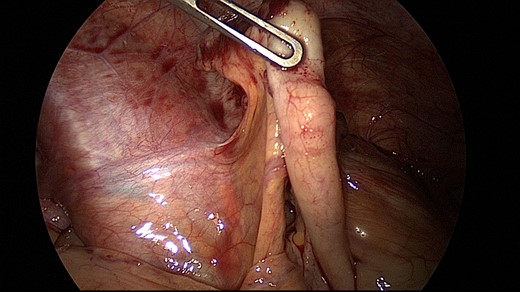

A 26-year-old nulliparous woman presented with right lower and upper abdominal pain 3 days after laparoscopic right ovarian cystectomy (dermoid ovarian cyst) and myomectomy of a small subserous myoma. Intraoperatively, the abdominal organs including the appendix appeared inconspicuous (Fig. 1). She was discharged from the hospital with more abdominal pain than expected, but still in a normal range. The pain increased on her second postoperative day in the evening and the next day, it became severe with concomitant nausea and vomiting.